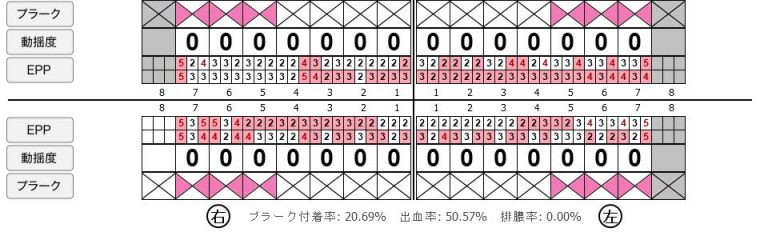

歯周病検査(治療前)

歯周病検査(治療後)

| 年齢・性別 | 41歳・男性 |

|---|---|

| 主訴 |

主訴:歯ぐきから出血する 治療部位:全顎 |

| 治療内容 | 1.歯周ポケット検査、資料取り(レントゲン写真14枚・口腔内写真)、歯磨き指導 2.歯磨き指導チェック、縁上の歯石除去 3.縁下の歯石除去4回 4.再評価(歯周ポケット検査・レントゲン写真14枚・口腔内写真) 5.メインテナンス |

| 治療期間 | 1日 |

| 治療費 | 合計:14,160円 内訳(全て保険診療3割負担) ・初診検査、歯磨き指導、縁上の歯石除去:3,630円 ・レントゲン写真、縁下の歯石除去①:3,040円 ・縁下の歯石除去②:1,530円 ・歯磨き指導チェック、縁下の歯石除去③:2,070円 ・縁下の歯石除去④:1,530円 ・再評価:2,360円 (2022年5月現在現在) |

| リスク・副作用 | ・歯石除去後すぐは歯ぐきを触っているため歯ぐきに違和感や痛みを感じる場合がある ・歯石除去により今まで腫れていた歯ぐきが引き締まり歯ぐきが下がる可能性がある ・歯ぐきが引き締まって下がることにより歯面が今までより露出し知覚過敏の症状がでる可能性がある ・歯石除去後、歯磨きを怠ると細菌が歯周ポケットのより深部まで入ってしまうため歯周病が悪化してしまう可能性がある ・一度歯周病になると再発しやすい為、定期的なメインテナンスが必要になります |

| 治療方針 | 1.歯磨き指導 2.歯ぐき上の歯石除去 3.歯ぐき下の歯石除去 4.再評価 5.定期的なメインテナンス |

| 特記事項 | ・着色除去(PMTC)は自費治療のため希望しませんでした。 ・右下7番の歯周ポケット5mmは親知らずの関係もあり、このまま維持していくことを説明しています。 ・他4mmの歯周ポケットに関しては歯垢が少し残っていた為、再度歯磨き指導と、縁下の歯石を確認して様子をみることにしました。 |

| 担当者所見 | 全体的に出血が見られたのと、奥の歯ぐきは炎症があり歯周ポケットが深かった為、まずは歯ブラシの当て方+歯間ブラシ3Sサイズを使用して頂き炎症を落ち着かせました。 両方毎日使用して頂いた為、スムーズに歯周病治療を行うことができました。毎日のホームケアが不十分だと、なかなか結果に繋がらず、治療期間も長くかかってしまう為、患者様の協力が歯周病治療を成功させるためにはかなり重要になっていきます。 そして一度病気になった歯ぐきは再発しやすい為、今後は3ヶ月に1度の定期的なメインテナンスで、この状態を維持できるよう一緒に管理していきます。 |